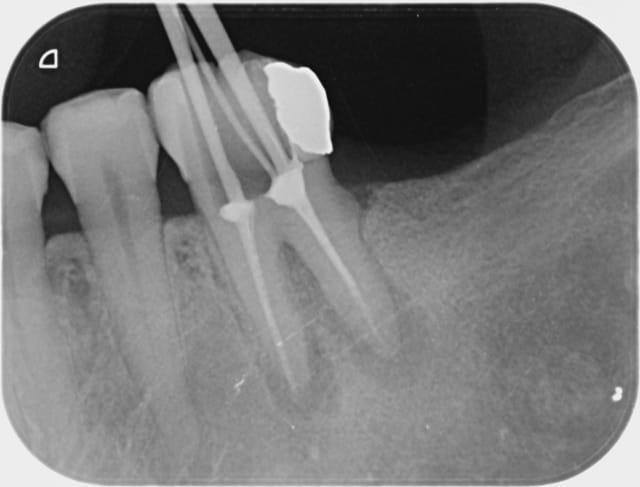

Pas plus tard que ce matin 11 h 30. Patient refoulé d'une premier cabinet, pour une bio sur une 8, qui le prenait en charge habituellement car la collègue n'arrivait pas à accéder à la 8. Envoyé à la fac dentaire, proposition d'intervention sous anesthésie générale ... Patient guère motivé qui échoue chez moi.

2 aiguilles plus tard ... radio curetage de la cavité ... "sans sushi" !

Je vous tiendrais au courant pour la pose de la digue.

Je vais t'aider : à supposer que tu aies fait ces radios sur une personne vivante et pas un crâne, je trouve complètement fou que tu préfères t'emmerder à faire des radios limes en place et pas mettre la digue, plutôt que mettre la digue et utiliser un localisateur d'apex qui t'évite de prendre des radios.

Maintenant, si c'est un clamp invisible, je trouve tout aussi inutile de prendre une radio, même avec la digue quand on peut utiliser un localisateur d'apex.